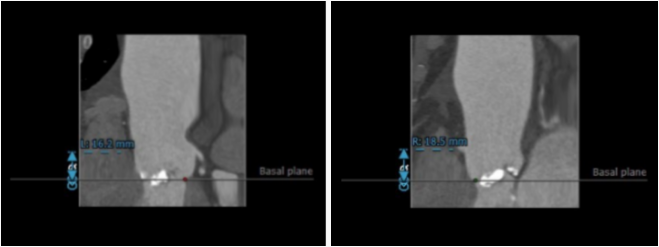

瓣环平面测量

定位两个窦底

瓣环平面周长82.5mm,直径26.3mm

(二叶瓣/极重度钙化)

选取合适的投射角度,两个窦底部在平面上,同时无冠窦在最低点

可以术中造影确认角度是否合适

横位心 接近90°